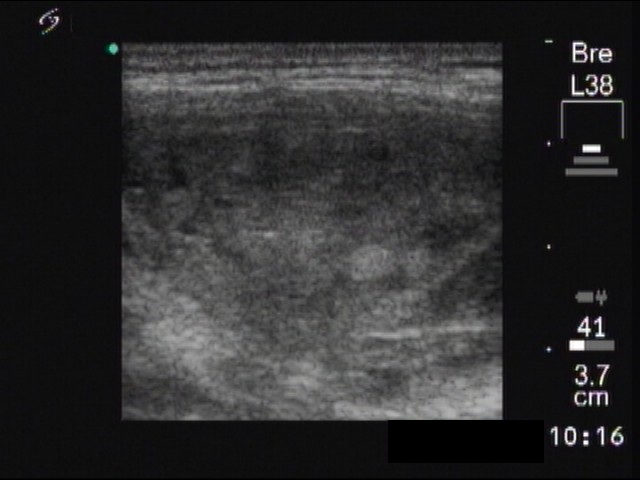

Ultrasonography : the thyroids were echonormal. There was a cystic nodule with an echonormal solid part in the right lobe.

Five sessions of sclerotherapy were performed. We gave 19.8 mL alcohol during five sessions of ethanol sclerotherapy. We demonstrate the first and the third sessions.

Follow-up examinations: the nodule decreased to 35x20x38 mm six weeks after the last session. Three years later the volume of the nodule was 55.8% of the pre-therapy volume. Generally, at least 50% reduction in volume is the requirement of the success of sclerotherapy. It means that the therapy was statistically unsuccessful. Nevertheless, the patient has no complaints, therefore he wished to continue follow-up instead of surgery or repeated sclerotherapy.